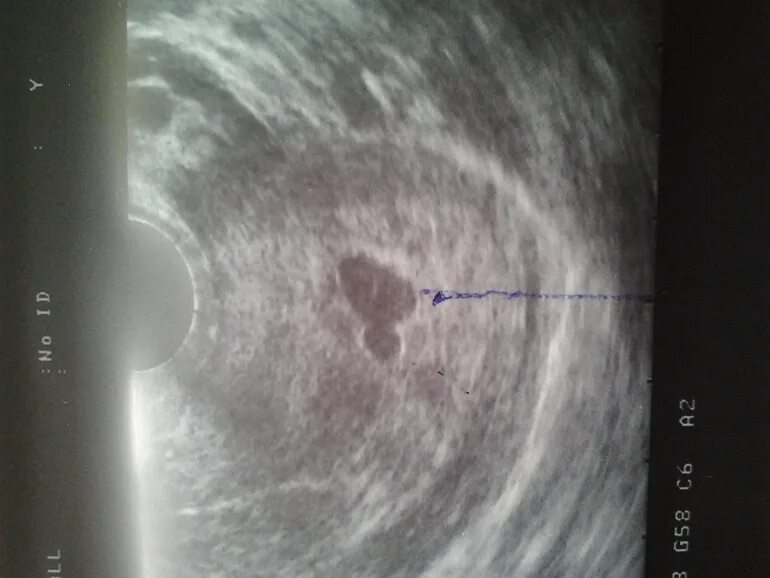

Как выглядит плодное яйцо на 5